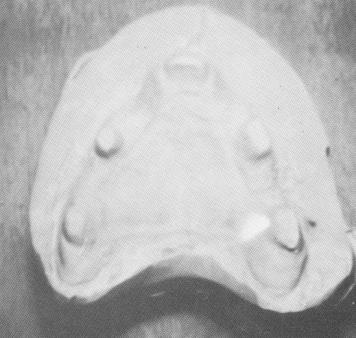

Fig. 10-227. The master stone model was poured from an elastic impression.

3 Maxillary master stone model poured from elastic impression